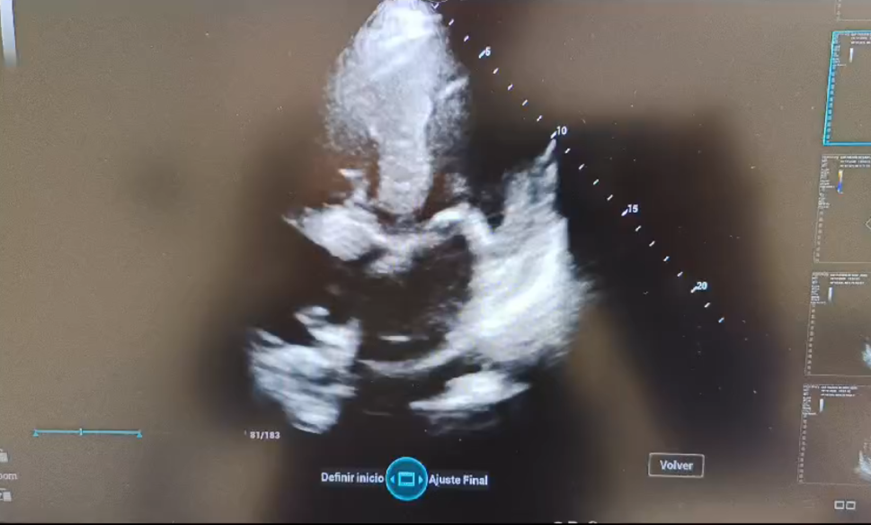

2.ª ecocardioscopia POCUS: derrame pleural, septo ventricular engrosado, hipoquinesia severa global, patrón de llenado ventricular restrictivo y derrame pericárdico.

La exploración convencional fue insuficiente para explicar la disnea y la congestión hepática, lo que motivó la realización de ecografía en Atención Primaria.